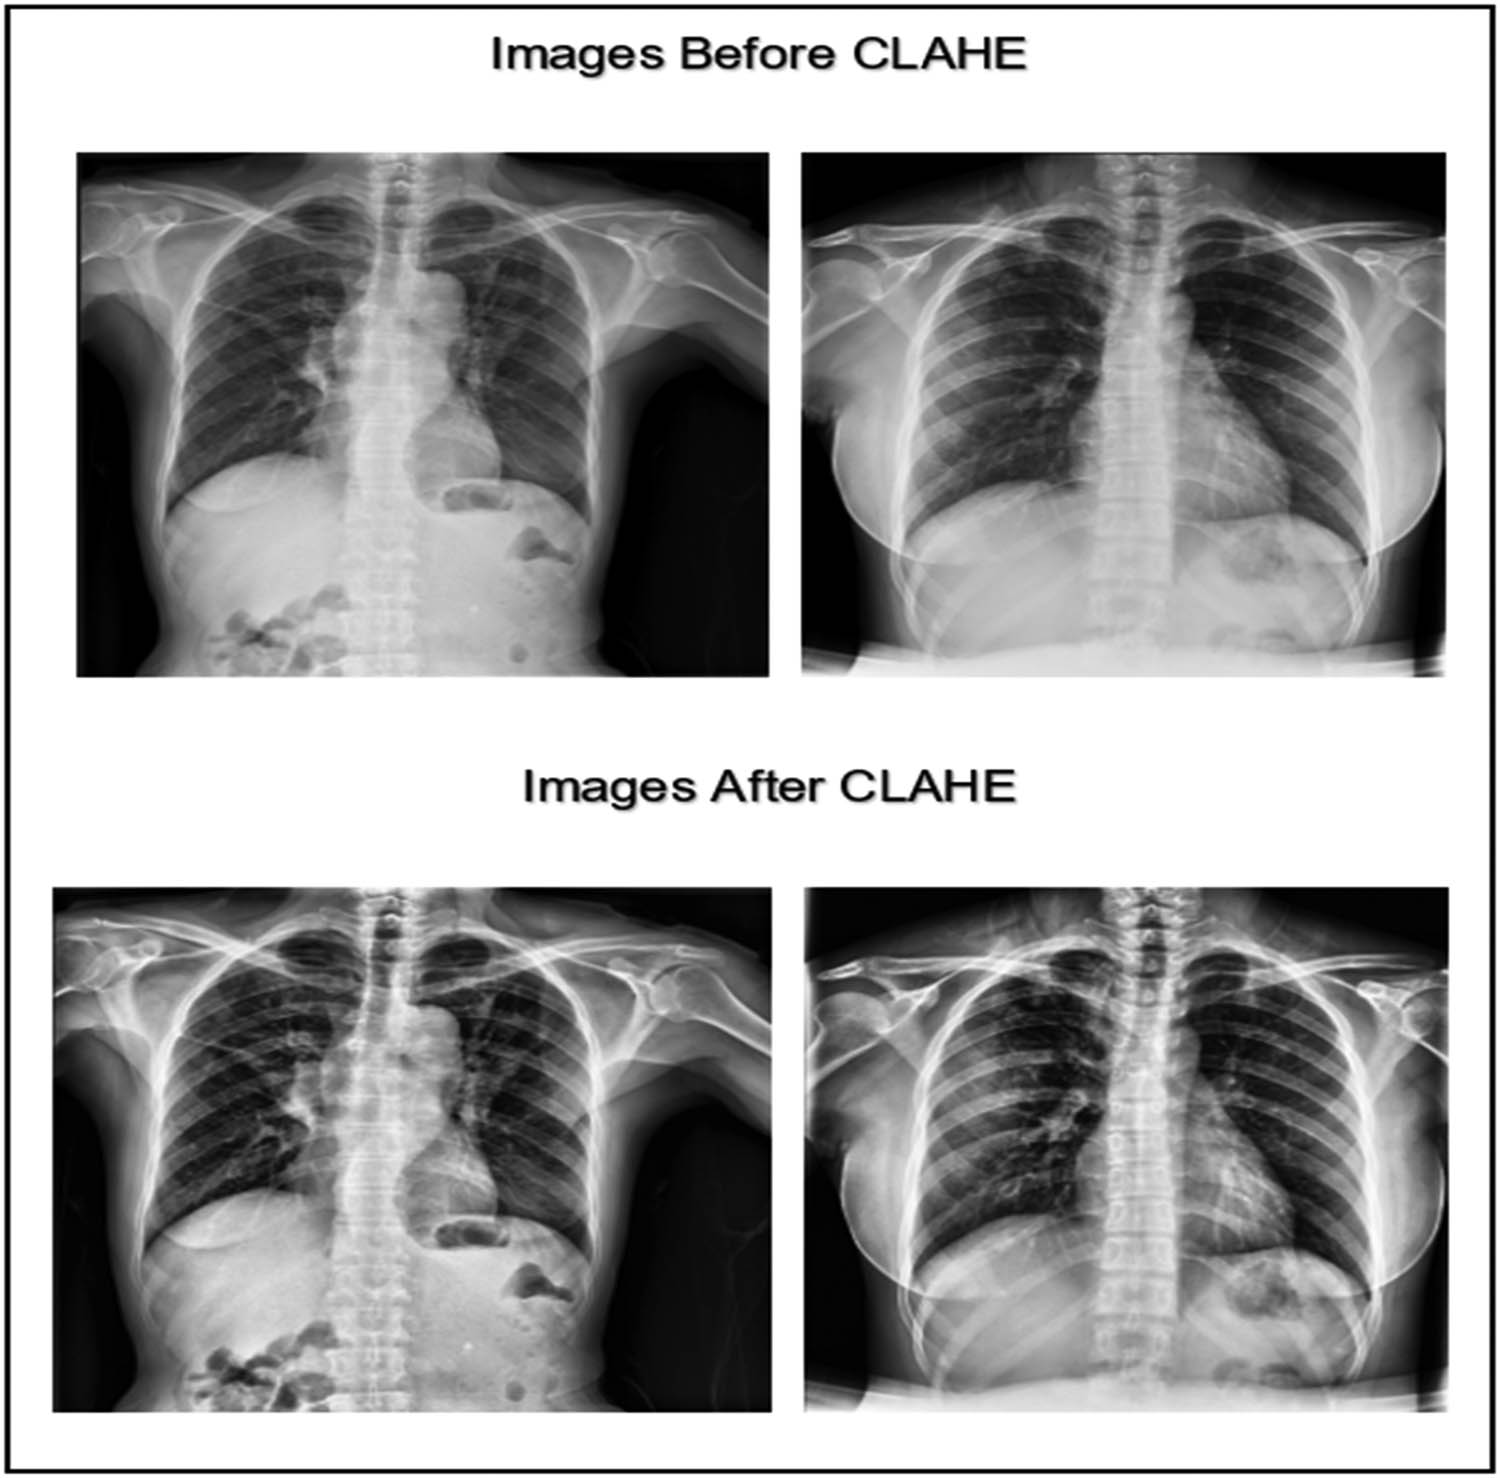

The CXR image dataset was collected from various sources. To achieve a high prediction accuracy for the classification, the images had to be clean, balanced, and enhanced. We utilized the CLAHE technique in the data preprocessing phase to enhance the images and improve their contrast [33]. CLAHE is an enhancement technique based on adaptive histogram equalization that can improve the visual contrast by expanding the intensity range or stretching out the most common intensity value found in the image [34]. The CLAHE technique splits the image into sub-images called “blocks” and then equalizes the histogram of each block separately, which helps to improve the contrast and the results in a very visible way. Figure 2 shows an example of the enhancement gained when using the CLAHE technique.

CXR images before and after applying the CLAHE enhancement technique (created by the authors).

Figure 3 displays the chart of the histogram of pixel distribution versus the gray levels in an image after applying the CLAHE technique. The chart shown indicates that the image has good contrast and high visibility because the pixel intensities are approximately evenly distributed across the range from 0 to 255.